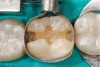

(2.) Preparation of tooth No. 31.

Figure 2